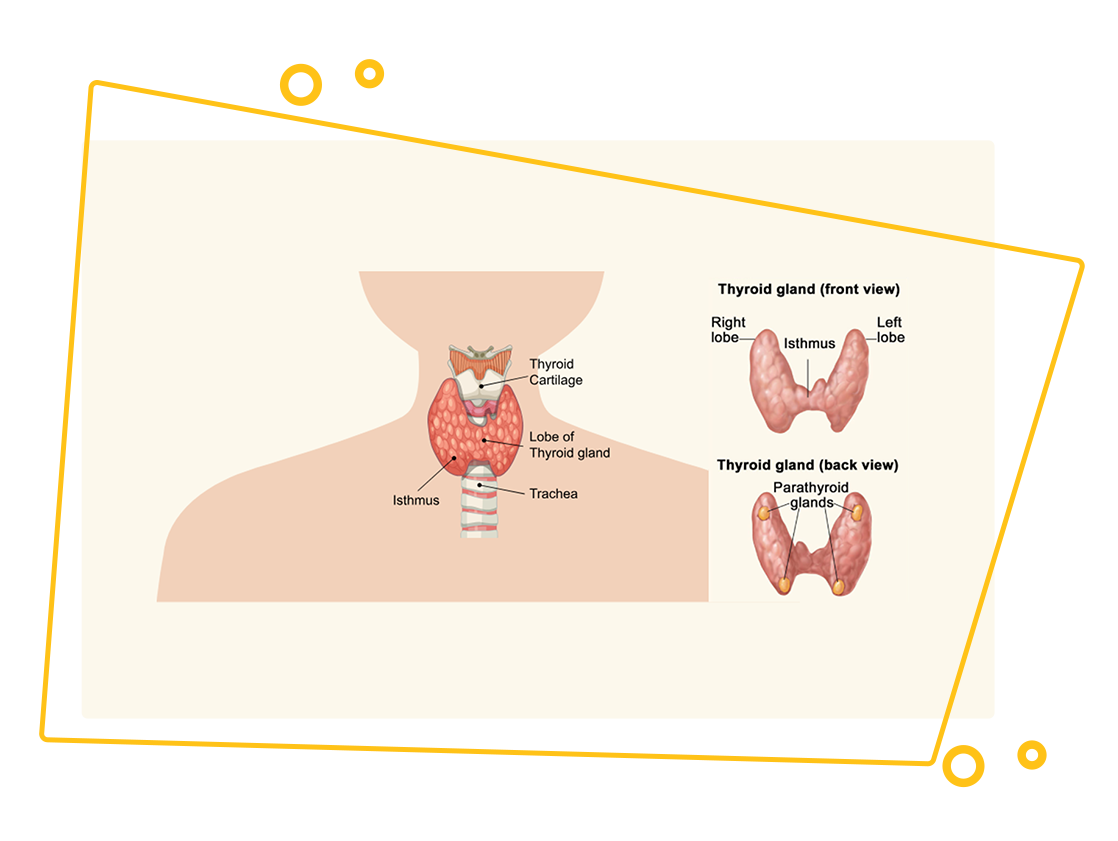

Thyroid / Parathyroid